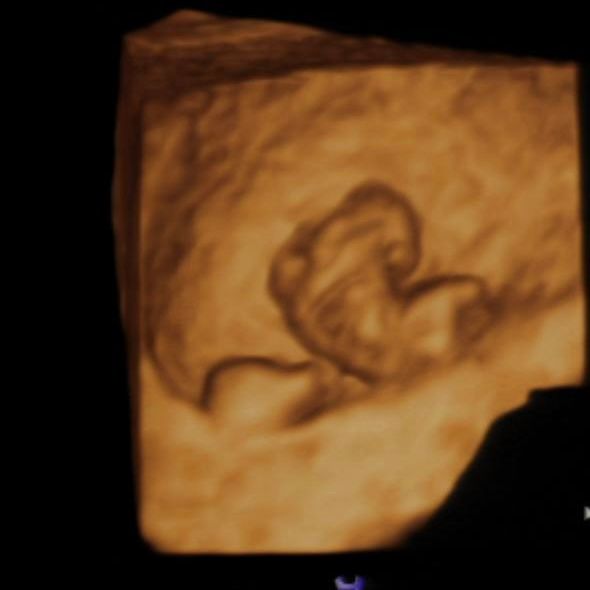

Результаты УЗИКТР 10.9, СБ 144 ❤️. Такой вот малышок (вчера делала УЗИ) 🫶. Соответствуем сроку, ручки, ножки формируются, 2 полушария в мозге, позвоночник. 4Д УЗИ.